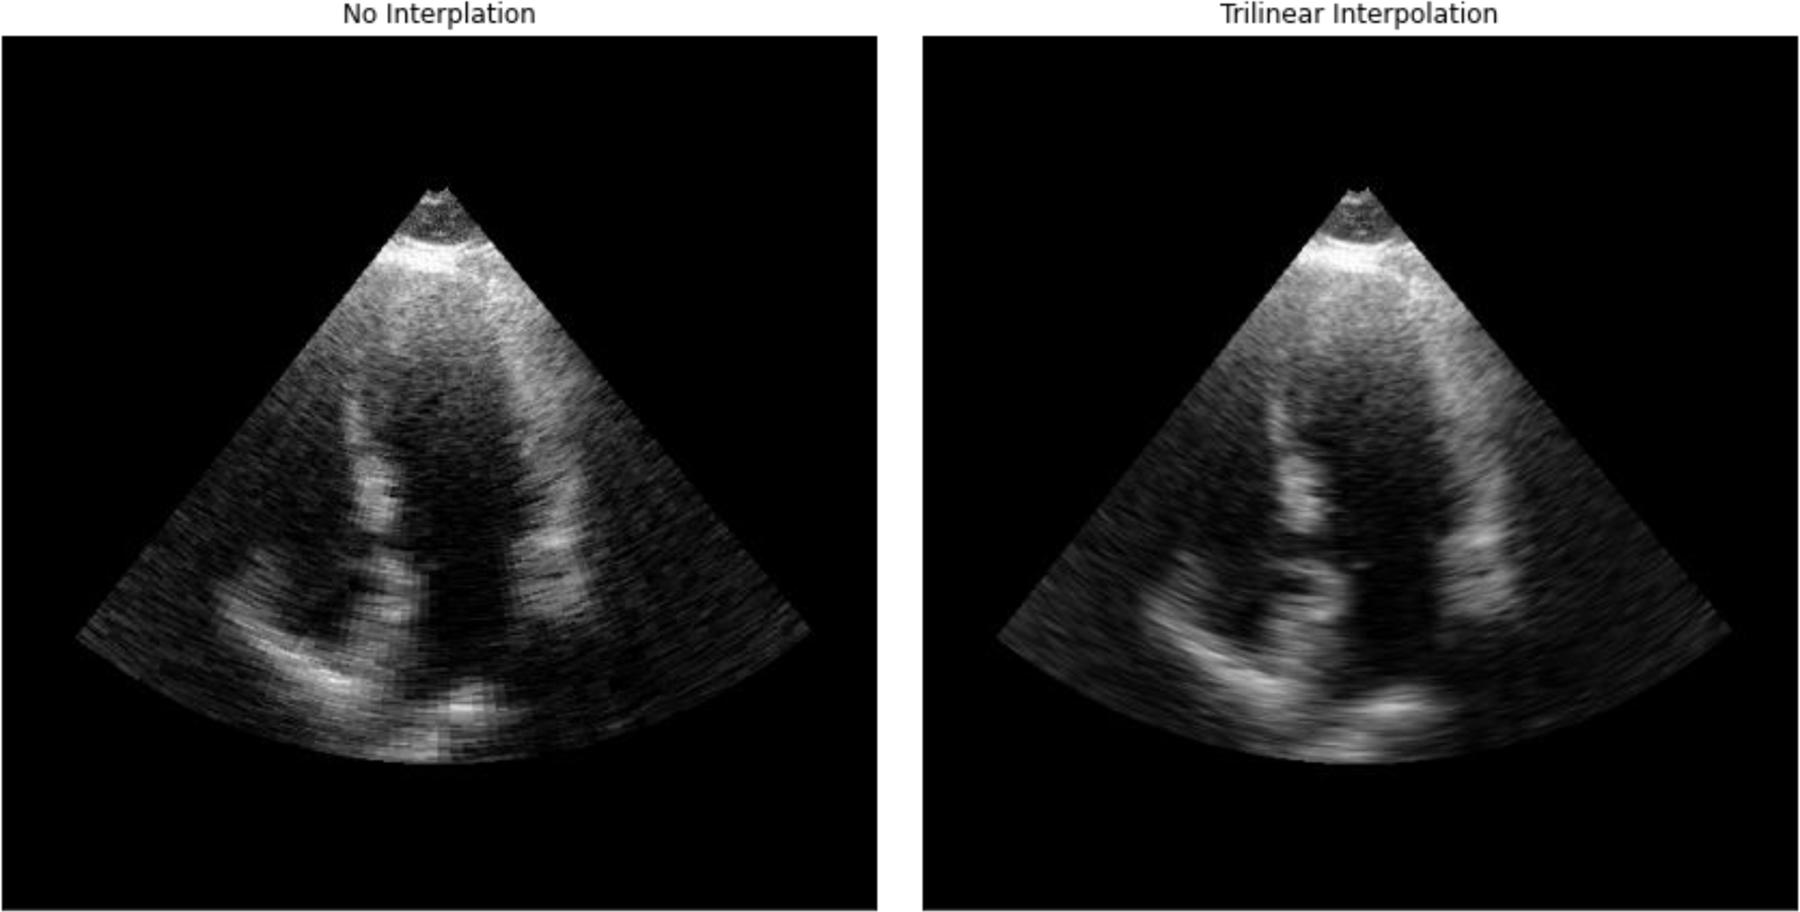

Advancements in medical imaging and artificial intelligence (AI) have revolutionized the field of cardiac diagnostics, providing accurate and efficient tools for assessing cardiac function. AI diagnostics claims to improve upon the human-to-human variation that is known to be significant. However, when put in practice, for cardiac ultrasound, AI models are being run on images acquired by human sonographers whose quality and consistency may vary. With more variation than other medical imaging modalities, variation in image acquisition may lead to out-of-distribution (OOD) data and unpredictable performance of the AI tools. Recent advances in ultrasound technology has allowed the acquisition of both 3D as well as 2D data, however 3D has more limited temporal and spatial resolution and is still not routinely acquired. Because the training datasets used when developing AI algorithms are mostly developed using 2D images, it is difficult to determine the impact of human variation on the performance of AI tools in the real world. The objective of this project is to leverage 3D echos to simulate realistic human variation of image acquisition and better understand the OOD performance of a previously validated AI model. In doing so, we develop tools for interpreting 3D echo data and quantifiably recreating common variation in image acquisition between sonographers. We also developed a technique for finding good standard 2D views in 3D echo volumes. We found the performance of the AI model we evaluated to be as expected when the view is good, but variations in acquisition position degraded AI model performance. Performance on far from ideal views was poor, but still better than random, suggesting that there is some information being used that permeates the whole volume, not just a quality view. Additionally, we found that variations in foreshortening didn't result in the same errors that a human would make.